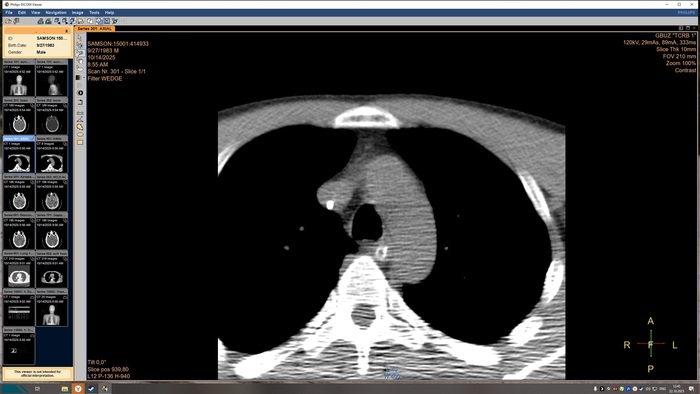

не выявлено. На прямой топограмме, серии аксиальных срезов и реконструкций получены

изображения органов грудной клетки от уровня верхней апертуры грудной клетки до уровня

задних рёберно-диафрагмальных синусов в нативном виде. Легкие в полном объёме,

пневматизация снижена. Справа в С3 выявляется бронхопневмоническая инфильтрация.

Конфигурация и просвет стволовых бронхов сохранены. Средостение обычной формы и

положения, дополнительных образований в нём не выявлено. Внутригрудные

бифуркационные и парааортальные лимфатические узлы не увеличены. Анатомия крупных

сосудов не нарушена, размеры в пределах нормы, стенки аорты и венечных артерий с очагами

кальцинатов. Плевральные утолщения и скопления жидкости отсутствуют. Диафрагма и мягкие

ткани грудной клетки без видимых патологических изменений. Признаков остеолитического, -

пластического процессов, травматических повреждений костных структур на исследованном

уровне не выявлено. ДИ по типу остеохондроза.

Заключение

КТ-признаки очаговых образований головного мозга. КТ-признаки правосторонней

верхнедолевой сегментарной б/пневмонии. ДИ ГОП.

Снимки КТ